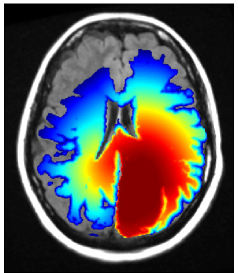

Refer to caption

Figure 10: GBM located in the left parietal lobe adjacent to the falx: (a) T2-FLAIR image with manual CTV (green) and model derived CTV (red); (b) simulated tumor cell density.

A.2 Parietal lobe case

Figure 10a shows the T2-FLAIR image of a GBM located in the left parietal lobe. Compared to the case discussed in section 3, the tumor is located more posteriorly and closer to the falx. The simulated tumor cell density for Dw/Dg=100subscript𝐷𝑤subscript𝐷𝑔100D_{w}/D_{g}=100 is shown in figure 10b. Similar to the case discussed in section 3, the tumor growth model simulates the infiltration of the contralateral side via the corpus callosum. The comparison of model derived target volume (red) to the manually drawn CTV (green) in figure 10a reveals that the tumor growth model suggests further spread into the contralateral hemisphere.